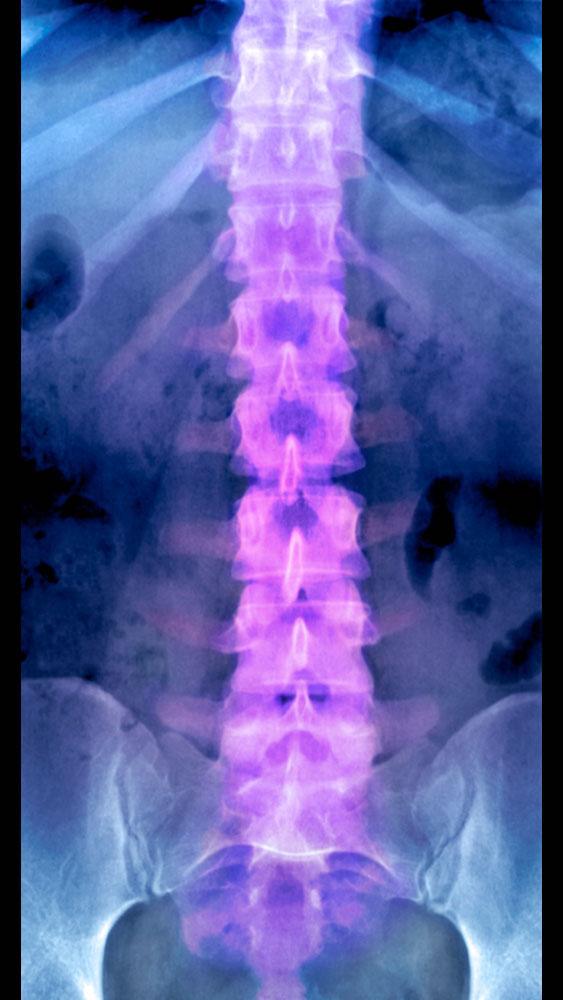

© Science Photo Library

• Aufbau: geformt wie ein Doppel-S, besteht aus verschiedenen Abschnitten von Hals-, Brust- und Lendenwirbelsäule bis zu Kreuz- und Steißbein, dazu 33 Wirbel, Bandscheiben, Bänder, Muskeln und Nerven

• Funktionen: verleiht einerseits Stabilität durch feste knöcherne Strukturen, ermöglicht andererseits enorme Beweglichkeit durch Wirbel, Bandscheiben und Gelenke, schützt Rückenmark und Nerven, sorgt für Kommunikation zwischen dem Körper, Gehirn und Rückenmark über die Spinalnerven

Wirbelsäule: Aufbau und Anatomie

Die Wirbelsäule ist eine knöcherne Struktur und der wichtigste Stützapparat für den menschlichen Körper. Sie sorgt dafür, dass ein Mensch beweglich ist, aufrecht gehen und sich bücken, drehen oder strecken kann. Durch ihre Anatomie schafft die Wirbelsäule aber auch Stabilität, um das Gewicht von Kopf, Armen und Rumpf tragen zu können. Für diese Aufgaben besitzt sie nicht nur bewegliche, sondern auch feste Bestandteile. Die Wirbelsäule verbindet verschiedene Teile des Skeletts miteinander: Kopf, Brustkorb, Schultern, Arme, Becken und Beine.

Die Wirbelsäule zieht sich als knöcherne Struktur durch den gesamten Rücken. Sie reicht von oben vom Hinterkopf (Halswirbel), über die Brust (Brustwirbel) bis hinunter zur Lende (Lendenwirbel) und zum Kreuz- und Steißbein. Es lassen sich jedoch verschiedene Abschnitte der Wirbelsäule beim Menschen unterscheiden.

Wirbelsäule – geformt wie ein doppeltes S